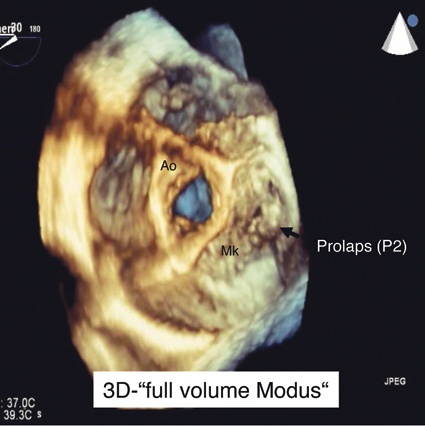

3. „Full-volume"-Modus (Abb. 3): 3-D-Untersuchung mehrerer pyramidenartiger Sektoren (meist 4-7 Untersektoren). Bei diesem Modus werden mehrere Untersektoren gewählt und in 4-7 konsekutiven Herzzyklen benachbarter Volumensegmente zusammengefügt, sodass die umliegenden Strukturen genau betrachtet werden können (Bildfrequenz 25-40 Hz).

Am Beispiel eines jungen Patienten mit Palpitationen möchten wir den Stellenwert der dreidimensionalen Echokardiografie darlegen. Die primäre transthorakale 2-D-Echokardiografie war aufgrund von schlechten Schallbedingungen nicht aussagekräftig, sodass die Indikation zur transösophagealen Echokardiografie bestand. Im Rahmen der 2-D-TEE Untersuchung im x-Plane-Modus konnten eine systolische Vorwölbung bzw. eine abnorme Protrusion des posterioren Mitralsegels (P2) nach atrial während der Ventrikelsystole mit exzentrischem Refluxjet im Farbdoppler nachgewiesen werden (Abb. 1), sodass die Diagnose eines Mitralklappenprolaps gestellt wurde. Zur weiteren räumlichen Zuordnung und Größenabschätzung des Mitralklappenprolaps erfolgte die 3-D-TEE-Untersuchung (Abb. 2 und 3), bei welcher der 2-D-TEE-Befund bestätigt werden konnte. Anhand der dreidimensionalen Darstellung war erstmalig eine genaue Größenzuordnung und Lagebestimmung des Prolapes möglich, sodass in Zusammenschau aller Befunde die Indikation zur herzchirurgischen Mitralklappenrekonstruktion gestellt wurde. Anhand dieser Falldemonstration erklärt sich gerade die Stärke der 3-D-Echokardiografie, da es dadurch gelingt, die komplexe sattelförmige Geometrie der Mitralklappe in einem plastischen Gesamtbild zu veranschaulichen. Der interventionell tätige Kardiologe und der Kardiochirurg erhalten zum einen eine orientierte Pathomorphologie in Echtzeit und zum anderen eine räumliche Beziehung zwischen prolabierenden und nicht prolabierenden Mitralsegelsegmenten.